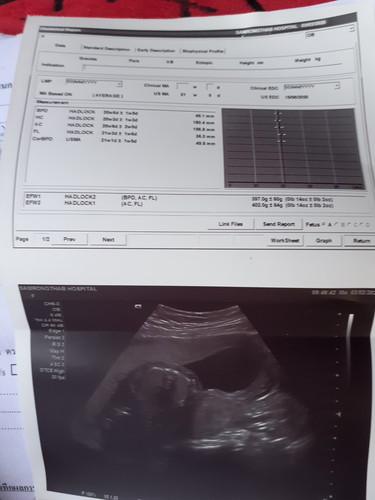

แม่ๆช่วยดูหน่อยคะ

น้องน้ำหนักเท่าไหร่แล้ว

นี่ค่ะ

ตั้งครรภ์